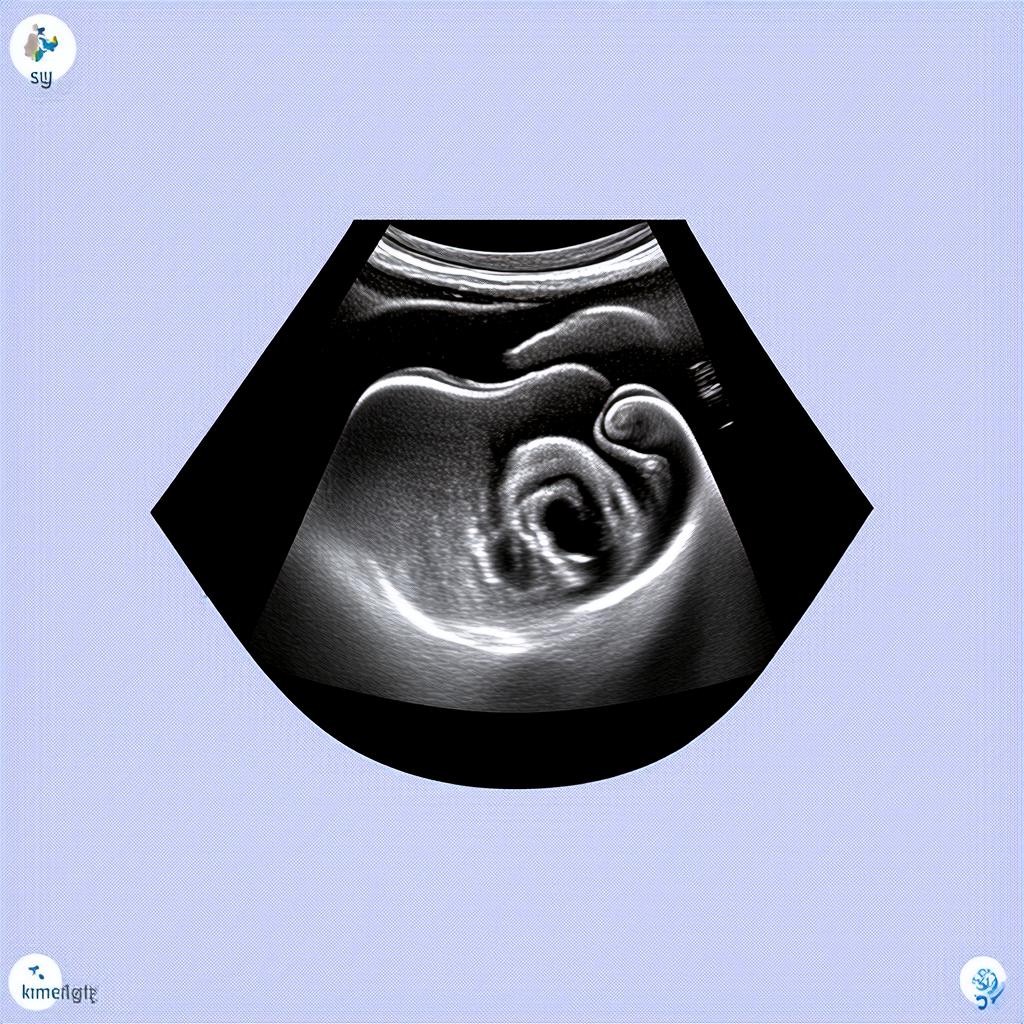

20 недель беременности — это важный этап, когда будущие родители могут узнать пол своего малыша. Ультразвуковое исследование (УЗИ) на этом сроке является частью второго скрининга и позволяет не только определить пол ребенка, но и оценить его развитие. Если врач сообщает, что у вас будет девочка, это повод для радости и подготовки к рождению малышки.

УЗИ на 20 неделе беременности проводится трансабдоминально, то есть через живот. Процедура безопасна для матери и ребенка и занимает около 20-30 минут. Врач оценивает:

- Размеры плода (фетометрия)

- Состояние плаценты и околоплодных вод

- Работу сердца и других органов

- Половые признаки для определения пола